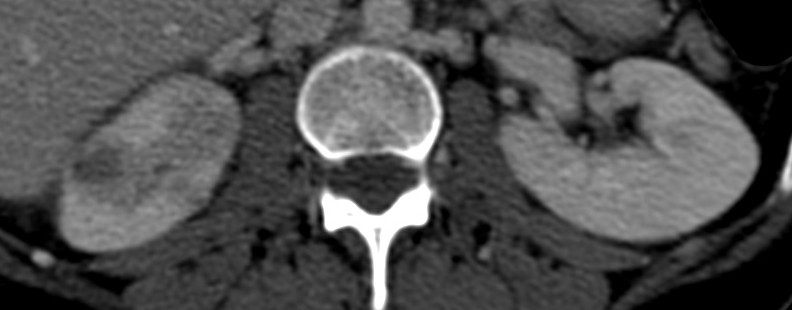

Se procede a realizar TC abdomino-pélvico con contraste en fase nefrográfica y excretora:

Conclusión: se nos presentó un caso de un paciente con una sospecha de infección renal complicada ya que tras cuatro días de tratamiento antibiótico no hubo mejoría. Ante los hallazgos observados en TC, podemos establecer el diagnóstico de pieloureteritis renal izquierda con signos de hidroureteronefrosis leve hasta vejiga.

- Protocolo: TC abominopélvico sin y con contraste en fase nefrográfica (70 seg) +/- fase tardía ( a los 7 – 10 min) solo si se sospecha obstrucción.

- TC con contraste: Las áreas afectadas del parénquima aparecen como zonas con baja atenuación debido al edema. Las áreas hiperdensas son menos frecuentes y corresponden a focos de hemorragia. Estos hallazgos son mejor valorables a través de la aplicación de contraste, ya que un TC en vacío pueden pasar desaprecibidas.